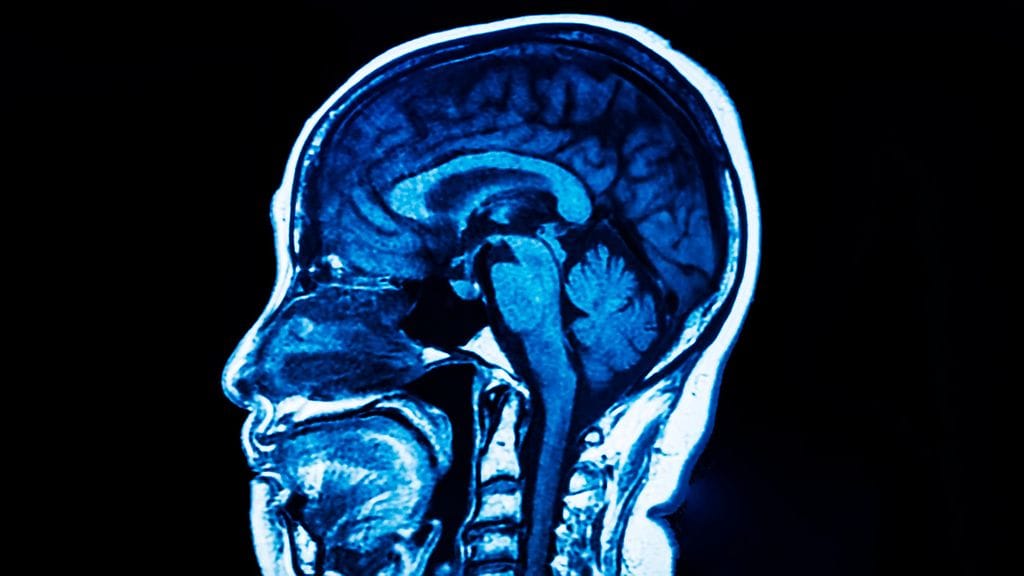

Aivoverenkiertohäiriöillä tarkoitetaan kaikkia aivojen verenkierron häiriöitä – siis ohimenevää aivoverenkiertohäiriötä eli TIA-kohtausta, aivoverenvuotoa ja aivoinfarktia. Pyörtyessäkin voi verenkierron todeta häiriintyneen, vaikka tila onkin yleensä hyvälaatuinen.